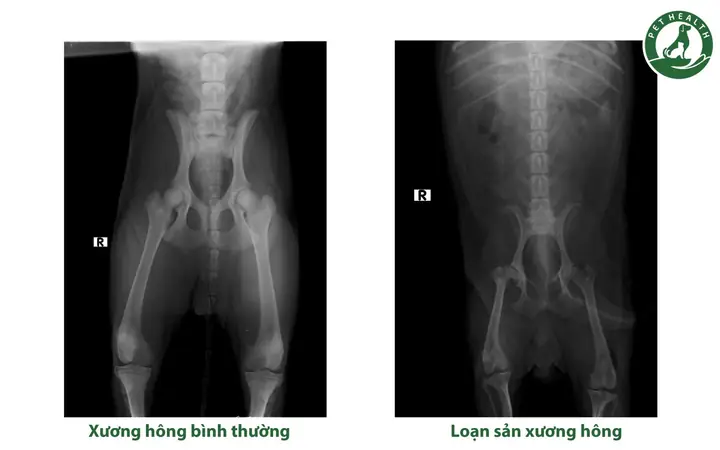

Chẩn đoán các vấn đề về xương khớp và chỉnh hình

Chụp X-quang là tiêu chuẩn vàng để chẩn đoán gãy xương, nứt xương, trật khớp và các biến dạng xương khác. Nó cung cấp hình ảnh chi tiết về cấu trúc xương, giúp bác sĩ xác định loại gãy xương, mức độ nghiêm trọng và vị trí chính xác để lên kế hoạch điều trị (bó bột, nẹp hoặc phẫu thuật). Bên cạnh đó, X-quang còn rất hiệu quả trong việc chẩn đoán các chứng loạn sản xương di truyền phổ biến ở một số giống chó lớn như loạn sản xương hông (Hip Dysplasia) và loạn sản khuỷu tay (Elbow Dysplasia). Phát hiện sớm các bệnh lý này qua X-quang cho phép áp dụng các biện pháp quản lý hoặc phẫu thuật kịp thời, cải thiện chất lượng cuộc sống cho chó và giúp các nhà lai tạo đưa ra quyết định chọn giống có trách nhiệm.